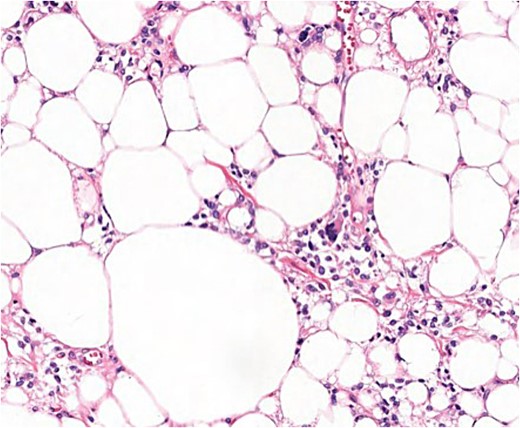

After the final diagnosis, surgery was scheduled in an ambulatory regime. Surgical excision of the tumour was performed generating a skin area defect on the left shoulder covered with a skin graft from the lateral aspect of the left thigh of the patient. The surgical piece presented lipomatous macroscopic characteristics with a total weight of 3110 g (Fig. 5). Under the microscope, floret-like spindle cells are presented, embedded together with mature adipocytes (Fig. 6).

Microscopic findings (H & E ×40): well-circumscribed lesion at the profound dermis, composed of mature adipocytes, with occasional pleomorphic lipoblasts and spindle cells in the stroma some of which presented ‘floret’-like morphology; focal areas of necrosis and absence of mitotic activity; intense and diffuse response to CD34.

Soft tissue tumours from benign and malignant origin can mimic clinical presentation needing the microscopic analysis to help clarify the differential diagnosis [6]. Under the microscope, PLs are characterized for presenting typical floret-like multinucleated giant cells (CD34+ and S100−) embedded in a myxoid stroma with a variable distribution of mature adipocytes (S100+). No signs of infiltrative growth, necrosis, or mitotic activity are found [6–8]. The presence of lipoblasts is not uncommon in PLs, being present in around 66% of the cases; therefore, it is not considered a distinguishable clinical feature of liposarcoma [9, 11].